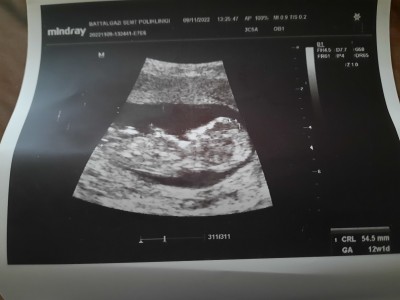

Tahmin cinsiyt lutfen

Tahminler lütfen

Gebelik haftası

11+6

Ben erkek diyorum. Hayırlısı olsun şimdiden